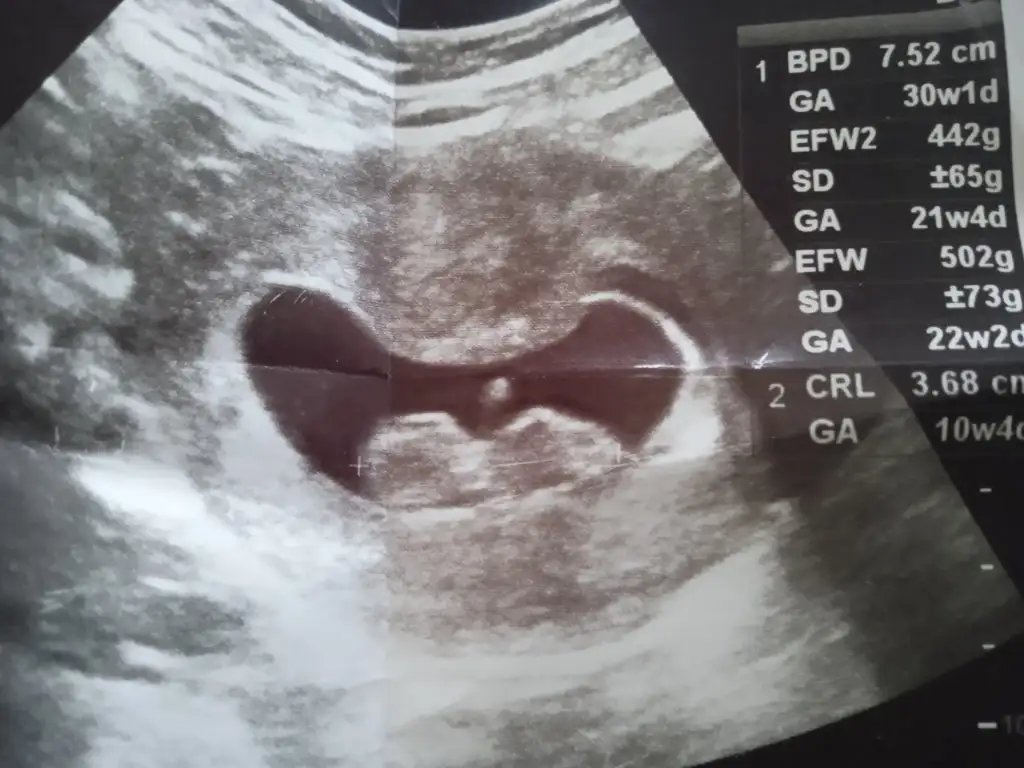

Sizce benimki neyNub teorisine göre kız![]()

Nub a göre kız canımMerhaba, 13.hafta ultrason görüntüsüne göre cinsiyet tahmini yapabilir misiniz

Bana bebeginiz kiz gibi geldi